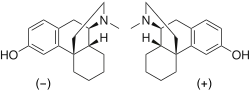

Morphinans

Morphinan series

- Levorphanol

- Levomethorphan

- Methorphan (racemethorphan)

- Morphanol (racemorphanol)

Structures

Dextromethorphan Dextromethorphan  levomethorphan levomethorphan |

Morphanol Morphanol |